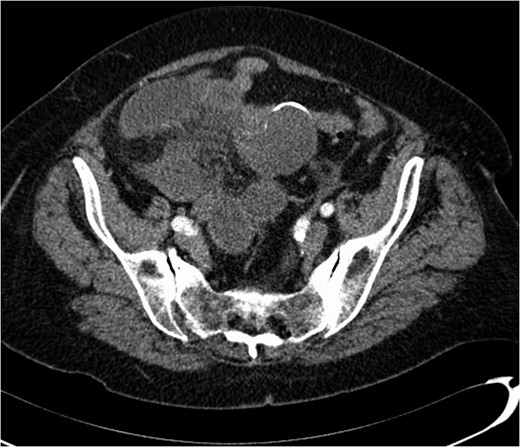

A 74-year-old female, with a background history of hypertension and hypothyroidism, presented to the emergency department with a 6-h history of sudden onset generalized abdominal pain. The pain was colicky in nature, associated with nausea and refractory to analgesia. Examination revealed tenderness in the right upper quadrant and epigastrium. Blood tests were normal except for a mild neutrophilia (7.5 × 109/l) and lactate of 2.5 mmol/l. A computed tomography (CT) scan of her abdomen and pelvis was performed which showed abnormal loops of small bowel along the right side of the abdomen with mesenteric fat stranding. A partially calcified structure was noted lying medial to the loops of bowel (Figs 1 and 2). The patient proceeded to have an explorative laparotomy performed. Intraoperative findings revealed an ischaemic loop of small bowel wrapped around a mass in the mesentery adjacent to the sigmoid colon (Fig. 3). The patient underwent a partial small bowel resection with primary anastomosis and en-bloc resection of the mass with the formation of an end colostomy. The final histological revealed a 6 × 4 × 4 cm cystic colonic duplication cyst separate but adjacent to the sigmoid colon. The inner lining of the cyst revealed mucinous epithelium, with mucin contained within. The wall of the cyst was sclerotic with occasional lymphoid aggregates, smooth muscle and neurovascular bundles (Fig. 4). The patient made a good recovery and was discharged home.

Intraoperative image black arrow pointing to intra-abdominal calcified structure. Ischaemic bowel in top left of image.